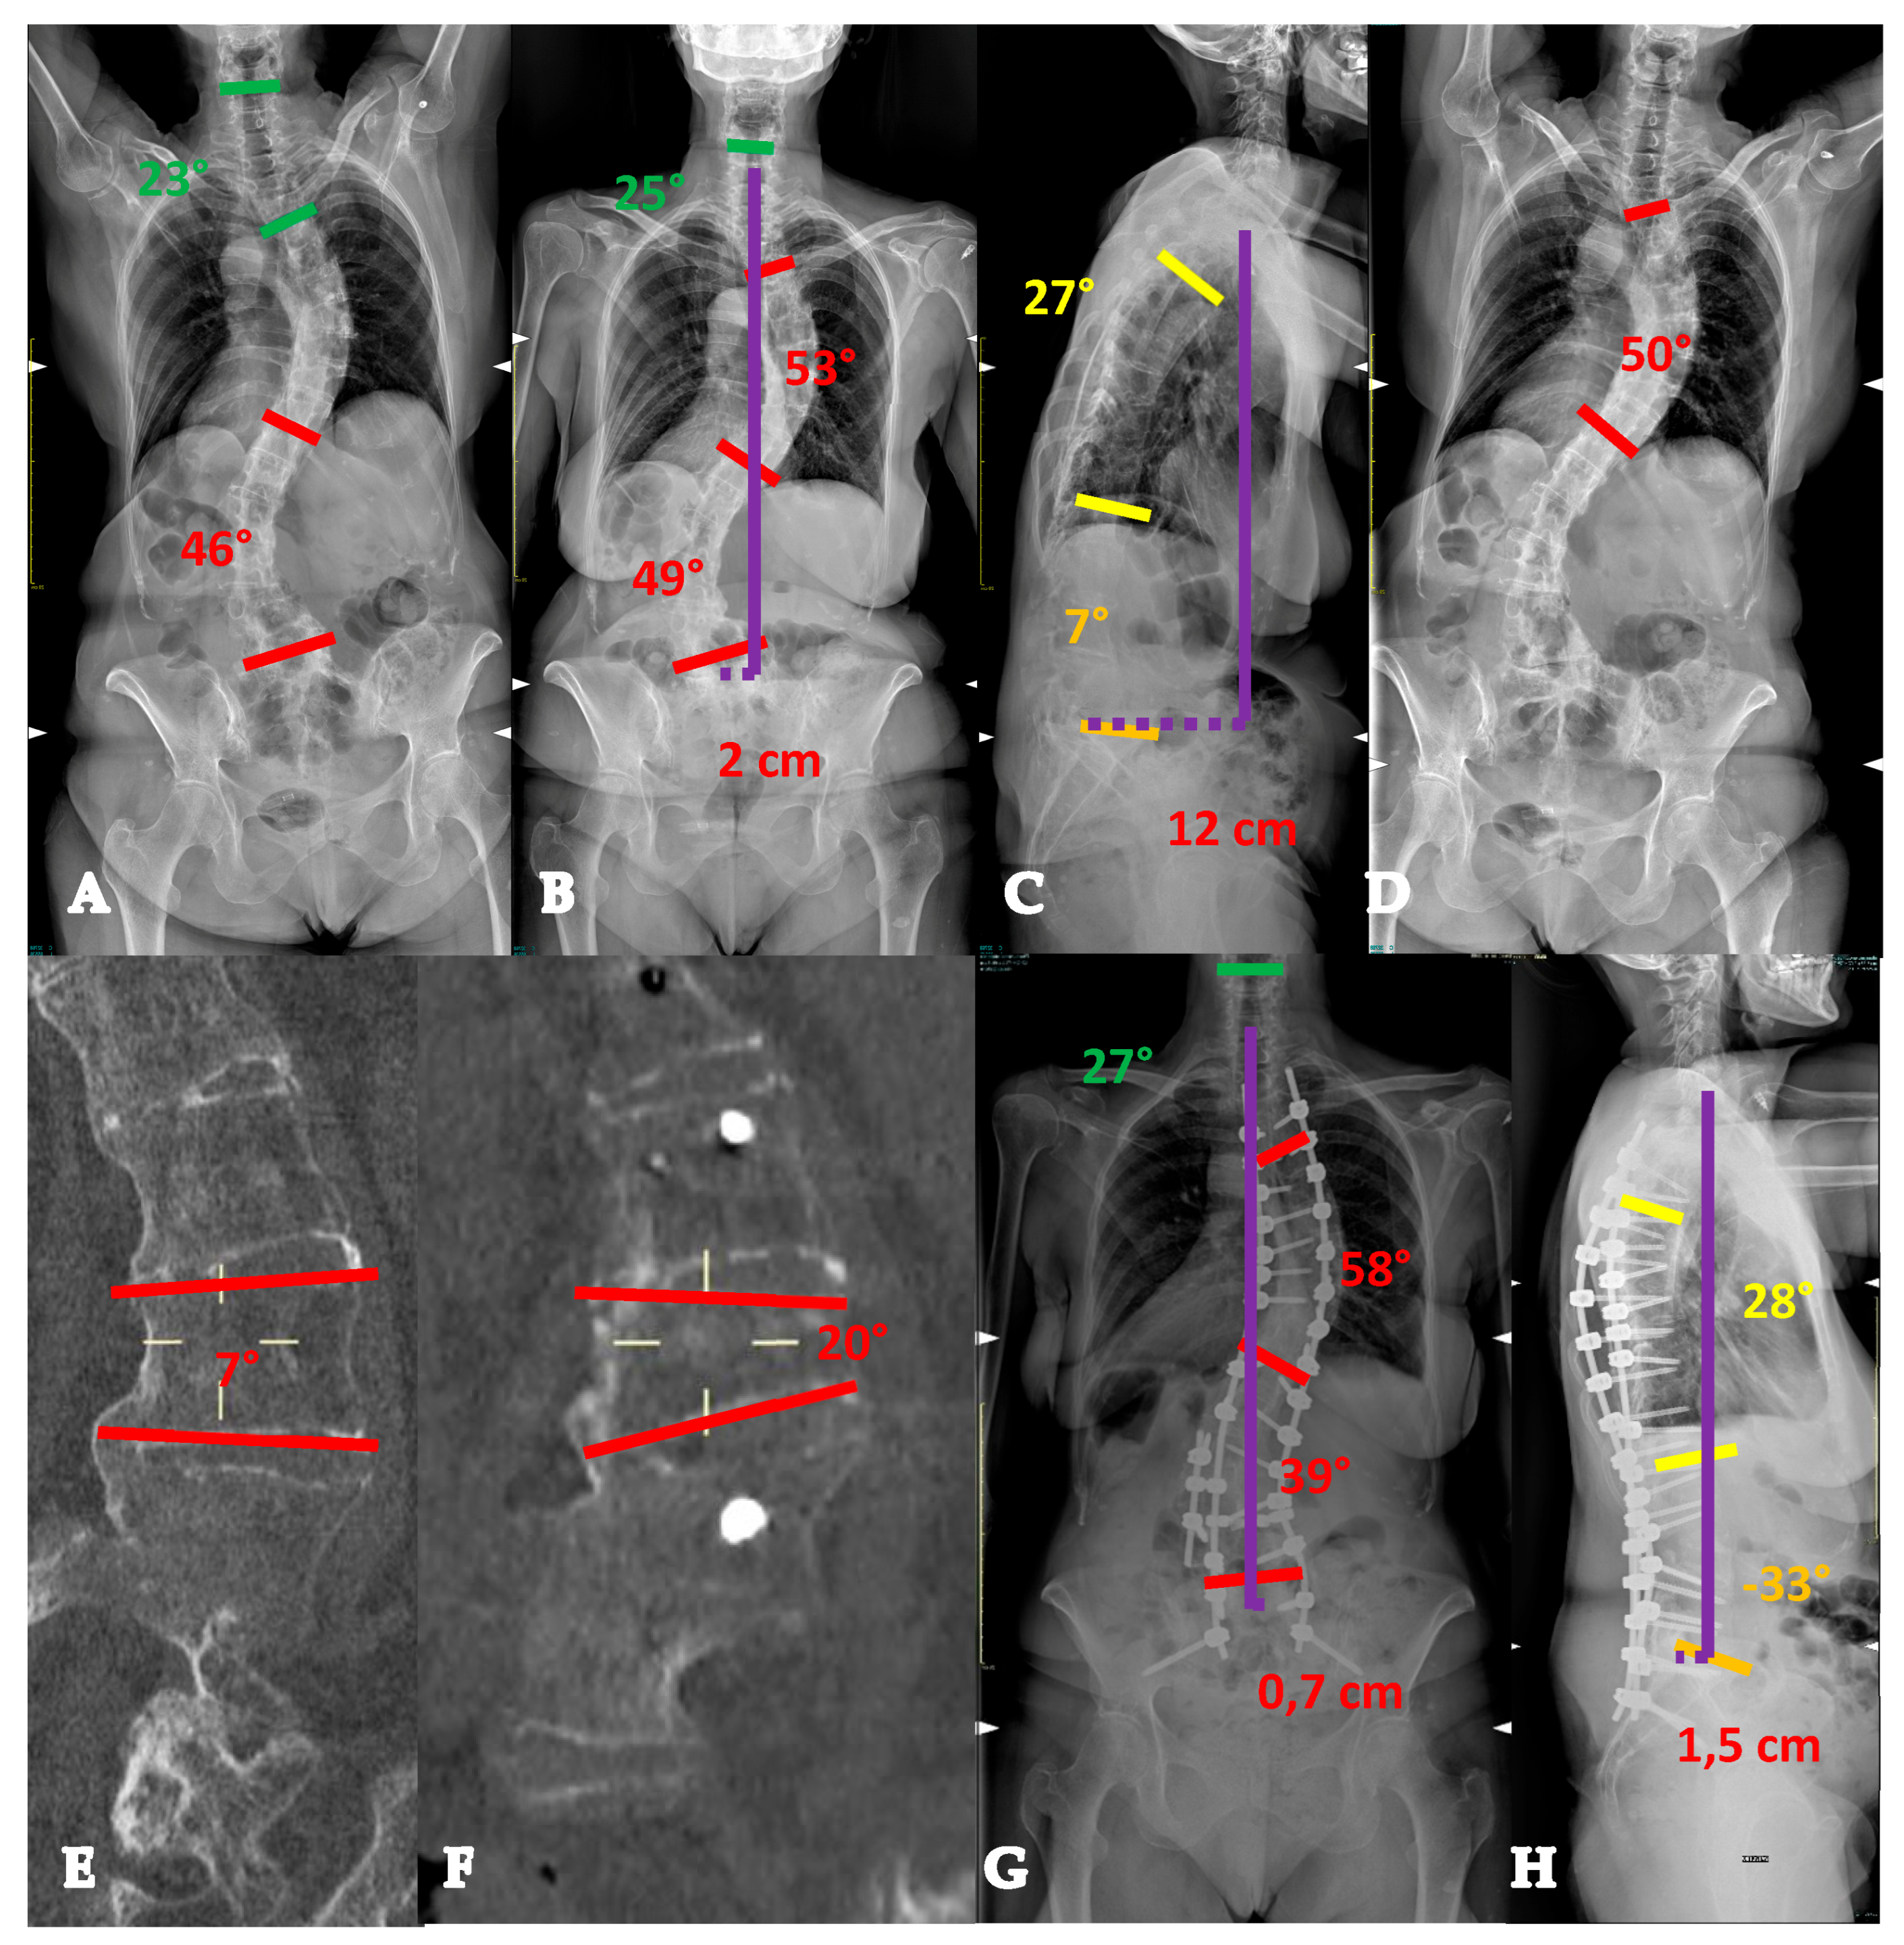

- For curves < 90° OR ≥90° and with a flexibility index > 15% (YADIS 2A), a combination of strategies with an all-posterior approach, already published by the authors under the acronym HiPoAD (High-Density Pedicle Screws, Ponte Osteotomies, Asymmetric Rods Contouring, Direct Vertebral Rotation) [10], may be sufficient to address the deformity. In particular, high-density constructs are preferrable in order to dissipate the corrective forces on every level and decrease the pull-out risks. Then, an aggressive posterior release based on multiple asymmetric Ponte osteotomies is of paramount importance, in order to allow an optimal deroto-translation over two asymmetrically contoured rods (Figure 3) [10,11].

- For curves ≥ 90° AND with a flexibility index < 15% (YADIS 2B), the HiPoAD technique, even though it proved to be effective for this kind of curve when addressed during adolescent years [12], may not be powerful enough for YAdIS 2 patients. These cases should be addressed with a three-columnar approach. One strategy could be to adopt three-column osteotomies like VCR. A possible alternative, in order to avoid the risks of a three-column osteotomy, is to perform a three-columnar release through a combined approach: an anterior thoracoscopic release (wide resection of anterior longitudinal ligament and multiple periapical discectomies), followed by a posterior column release based on multiple Ponte Osteotomies and a posterior correction (VT-HiPoAD, Videothoracoscopic release—HiPoAD) (Figure 4).